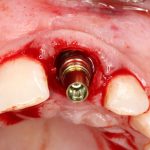

Для решения поставленной клинической задачи мы выбрали имплантационную систему Xive. Из имеющихся у нас трёх имплантационных систем, она лучше всего подходит для немедленной имплантации и немедленной нагрузки, и вот, почему:

В процессе ирригации лунки промываются, что позволило нам еще раз подтвердить ранее сделанные выводы. С помощью аналогов имплантатов, входящих в хирургический набор Xive, мы проверили возможность стабилизации имплантатов в будущих лунках. Исходя из правил подбора и позиционирования имплантатов (я очень рекомендую почитать об этом здесь>>) мы остановились на Xive S диаметром 3,4 мм и длиной 13 мм.

По ряду уже упомянутых выше причин, для решения этой клинической задачи мы выбрали имплантаты Xive. Лунки для них мы уже приготовили. возможную первичную стабильность оценили. Имплантаты мы установили с усилием чуть больше 15-20 Нсм — такого крутящего момента более, чем достаточно, особенно если учесть, что временные коронки будут соединяться между собой.

Подробно о том, что такое крутящий момент и хирургический протокол можно прочитать здесь>> и тут>>, соответственно. Из-за использования специальных индивидуализируемых временных абатментов, имеющих только три положения, нам нужно позиционировать платформу имплантатов по граням. Это очень просто  — мы выводим вырез абатмента TempBase (он входит в комплект поставки) вестибулярно.